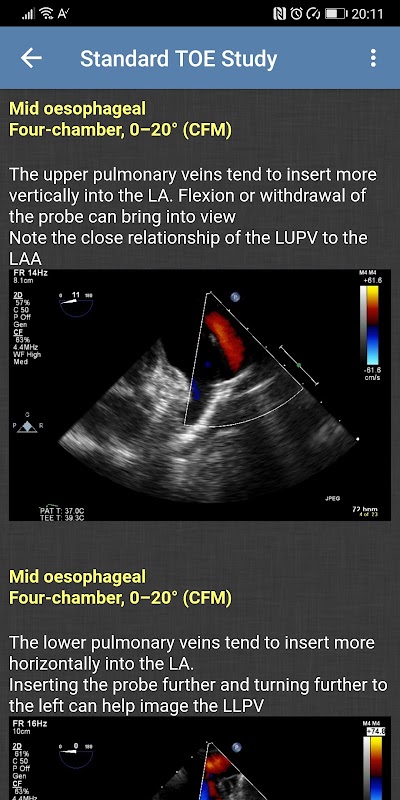

- Nghiên cứu TOE tiêu chuẩn